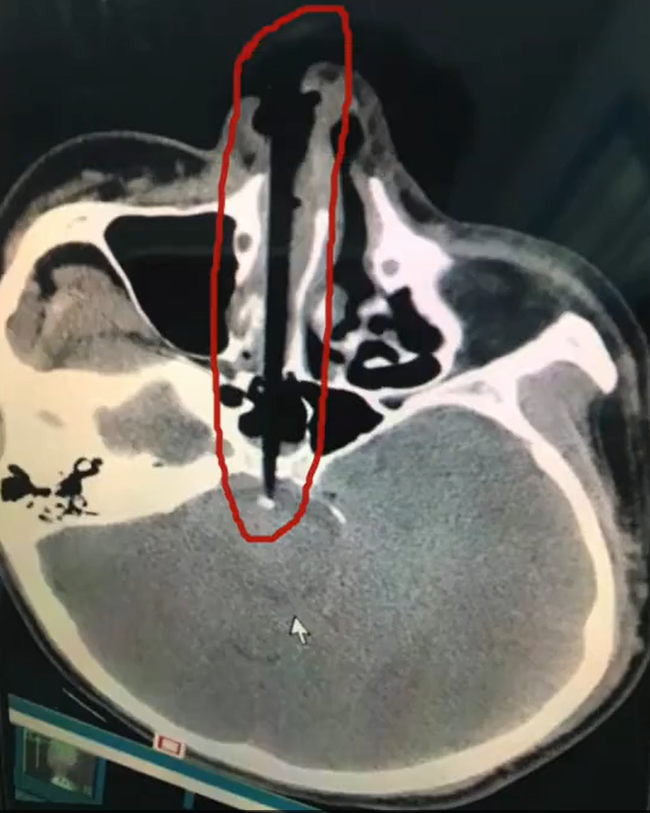

Old  Default Cây đũa hơn 20cm găm vào hốc mũi 1 nam thanh niên tại Trung Quốc vì lý do ngớ ngẩn này

Sau bữa ăn, 1 nam thanh niên tại Trung Quốc đã 'nhanh trí' lấy đũa để ngoáy mũi. Khi đứng dậy, anh bất ngờ vấp ngã và tạo lực đẩy cho cây đũa 20 cm đâm vào hốc mũi. Trải qua ca phẫu thuật và lấy chiếc đũa ra thành công, anh đang dần phục hồi và chờ ngày xuất viện

Theo trang Shanghaiist, một người đàn ông sống ở Hồ Nam, Trung Quốc cảm thấy ngứa ngáy trong lỗ mũi sau khi ăn tối với gia đình. Ngay khi mọi người đứng dậy rời khỏi bàn, không thể chịu đựng được cơn ngứa, anh ta đã với lấy chiếc đũa và làm điều không tưởng: Nhét cây đũa và lỗ mũi và bắt đầu ngoáy mũi không ngừng.

Nhưng điều tồi tệ nhất không phải là chiếc đũa đó vừa để ăn cơm mà lại dùng để ngoáy mũi. Khi anh ta đứng dậy, bỗng bị vấp ngã và mặt cắm xuống đất. Như mọi người có thể tưởng tượng, chiếc đũa 20cm đã cắm thẳng vào hốc mũi. Khi mọi người nghe thấy tiếng kêu thất thanh và quay trở lại phòng ăn, ai nấy đều hãi hùng trước cảnh tượng trước mắt.

Ngay lập tức, anh ta được đưa đến bệnh viện gần nhất, các bác sĩ tiến hành phẫu thuật cấp cứu vì sợ rằng bất kỳ chuyển động nhỏ nào cũng có thể khiến chiếc đũa đẩy sâu vào bên trong hộp sọ.

May mắn là ca phẫu thuật thành công, người đàn ông này hiện đang phục hồi tích cực và sớm ra viện